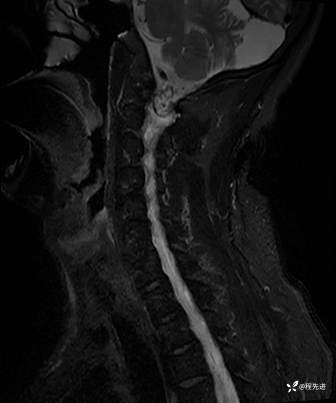

T2压脂: